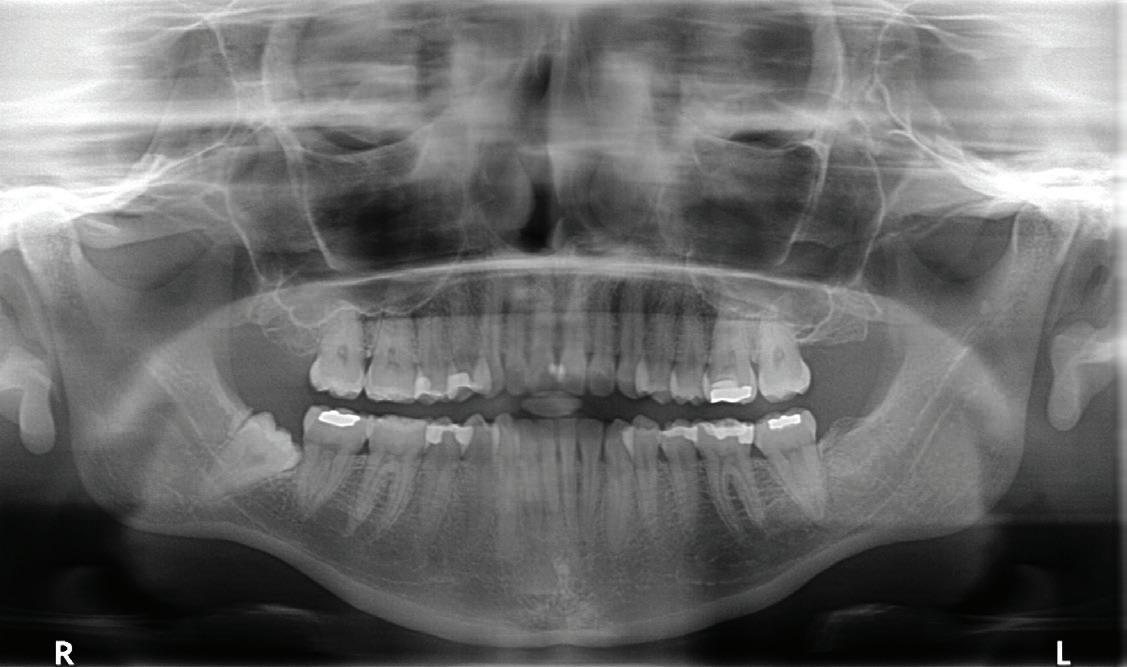

“Yes. You check for soft-tissue injuries, any suspected underlying hard-tissue injury and then imaging. A Panorex image is a good screening device, not only for dental trauma but also

for associated problems that may not be evident at first glance. Once you have a diagnosis, you can provide the appropriate treatment.”

Coronectomy isn’t usually recommended if the tooth or root is infected or in younger patients whose roots aren’t yet fully developed. Dr. Pogrel and his colleagues also found that “teeth that are horizontally impacted along the course of the [IAN] may be unsuitable for this technique because sectioning of the tooth itself could endanger the nerve.” But for other patients, coronectomy is indicated if a panoramic plain-film X-ray (often followed by a confirming cone-beam

computed tomography) shows that a root’s proximity to the IAN poses a danger of nerve damage.

Oral surgeon Rosie Noordhoek, DDS, says that there are some definite signs on panoramic X-rays that indicate a higher risk of sensory nerve damage: “when the root gets darker, for instance, or the nerve is displaced, or you can’t see the whole nerve canal.” To confirm that coronectomy is the preferable course, says Dr. Noordhoek, “we usually recommend a CBCT at that point.”

Pre-op panoramic 6 months post coronectomy